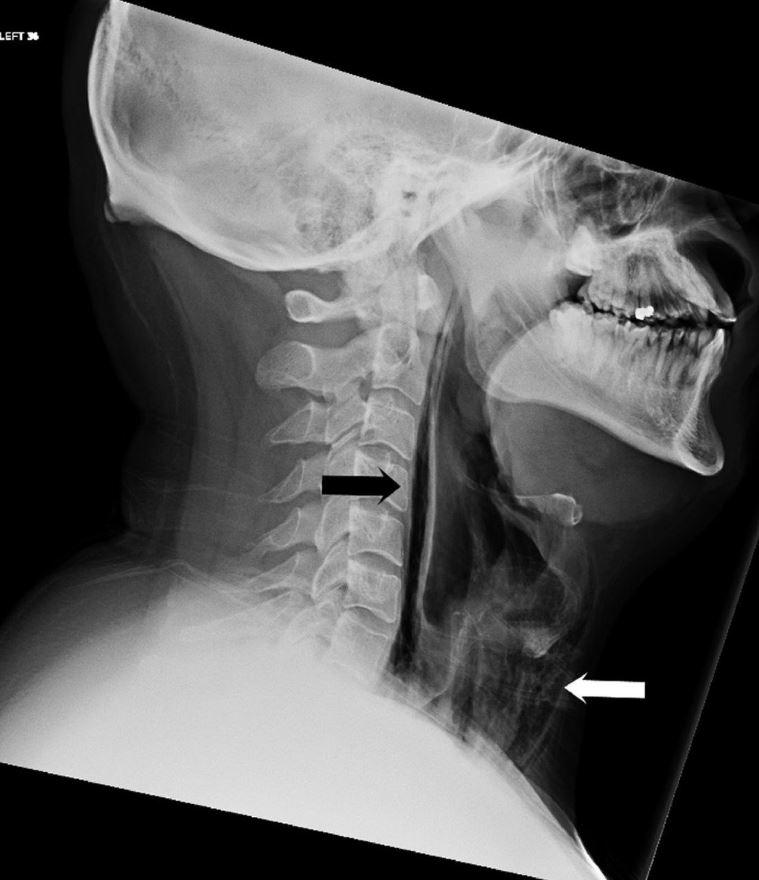

Οι γιατροί το αναγνωρίζουν αυτό με την ορολογία “σημάδι του Χάμαν”. Μπορεί να συμβεί όταν καθώς συστέλλεται και διαστέλλεται η καρδιά, χτυπάει πάνω σε ιστό γεμάτο με αέρα. Οι γιατροί διέταξαν επιτόπου να γίνει ακτινογραφία. Εκεί αποκαλύφθηκε το πρόβλημα:

Καθώς “κράτησε” το φτέρνισμα, ο 34χρονος είχε σπάσει το πίσω μέρος του λαιμού του!

Η ρήξη (η οποία προκαλείται συχνότερα από αμβλύ τραύμα στον λαιμό, έντονο έμετο και βαρύ βήχα) είχε προκαλέσει διαρροή αέρα στην οπισθοφαρυγγική περιοχή (δείτε το βέλος στην ακτινογραφία), προκαλώντας πόνο και απώλεια φωνής.